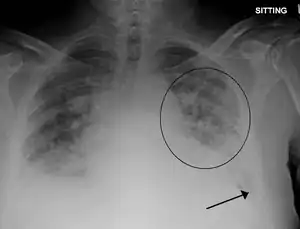

| Pulmonary edema with small pleural effusions on both sides | |

Low oxygen saturation in blood and disturbed arterial blood gas readings support the proposed diagnosis by suggesting a pulmonary shunt. A chest X-ray will show fluid in the alveolar walls, Kerley B lines, increased vascular shadowing in a classical batwing peri-hilum pattern, upper lobe diversion (biased blood flow to the superior parts instead of inferior parts of the lung), and possibly pleural effusions. In contrast, patchy alveolar infiltrates are more typically associated with noncardiogenic edema[3]